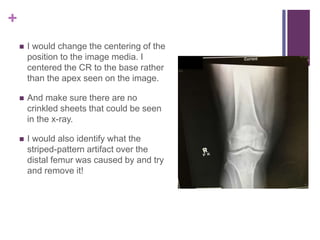

 I would change the centering of the

position to the image media. I

centered the CR to the base rather

than the apex seen on the image.

 And make sure there are no

crinkled sheets that could be seen

in the x-ray.

 I would also identify what the

striped-pattern artifact over the

distal femur was caused by and try

and remove it!